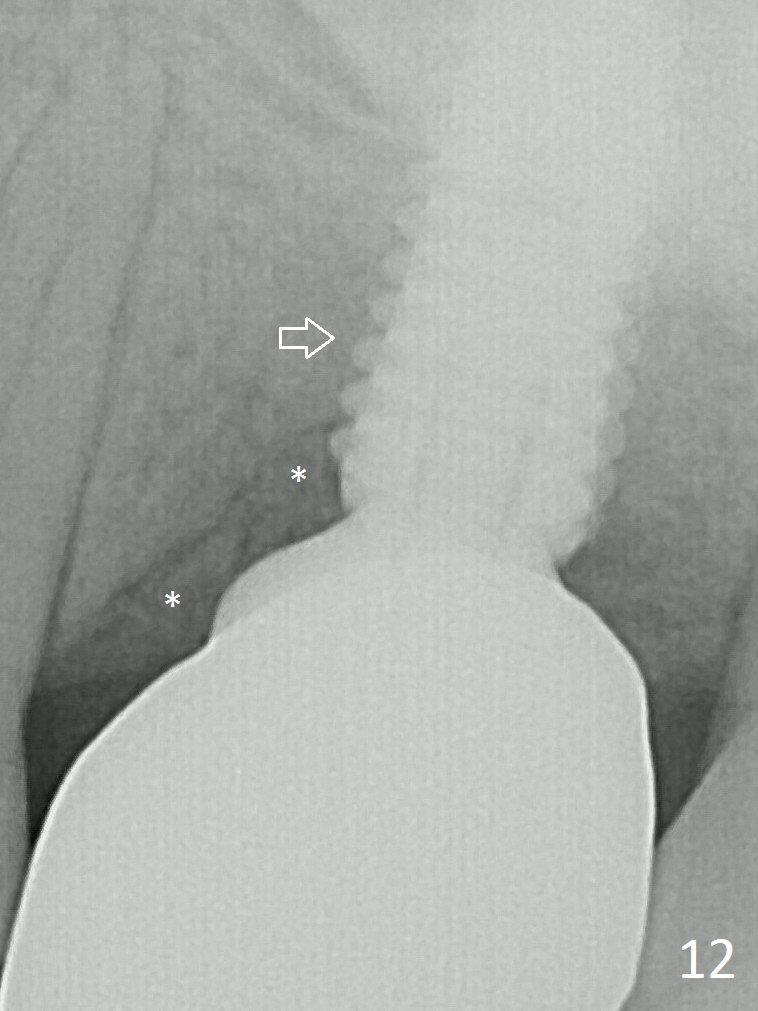

The patient experiences palatal gingival tenderness 5 months post cementation, probably due to loose proximal contacts and excessive use of floss. PA shows new normal bone next to the upper threads (Fig.12 arrow), while new less dense attached to the most coronal threads (*).